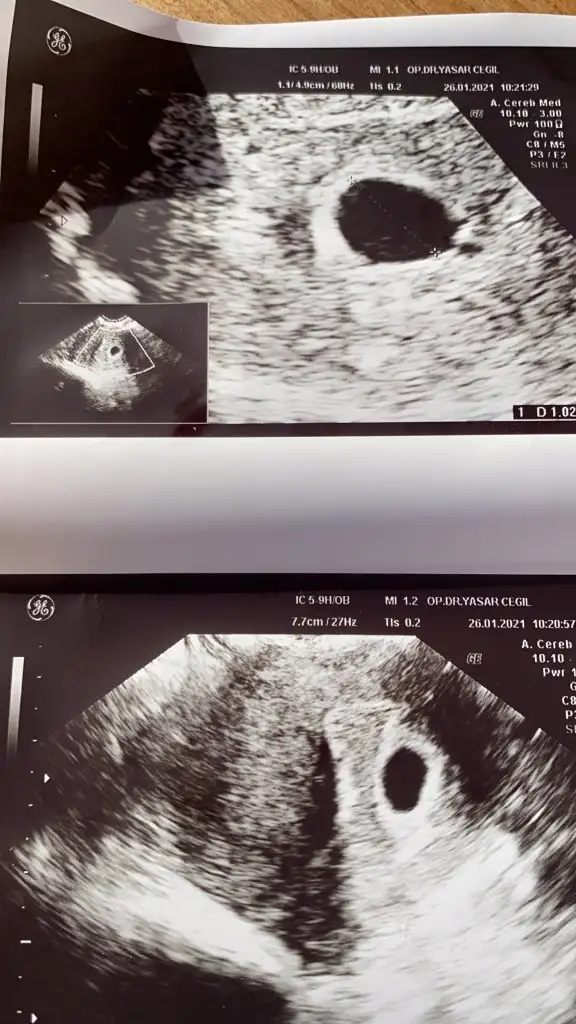

Gittim canım dr a ama çok iç açıcı değil şuan durum kese var ama bebişi görmedik kendi dr um erken dönemde olabiliyor böyle dedi 10 gün sonra tekrar gitcem. Moralim bozuldu çook 7+3 teyim şuan 21 aralıkta transfer oldu 25 aralık gibi tutunsa şuan 4 haftalık 2 hafta geri gittiğimde 6 hafta yapıyor valla aklım çok karıştı beklemekten başka çarem yok

İnşallah öyledir hayatım en iyisini rabbim bilir geçenki kontrole göre kese büyümüş ama bebişş hala yok nasip artık bekliycez